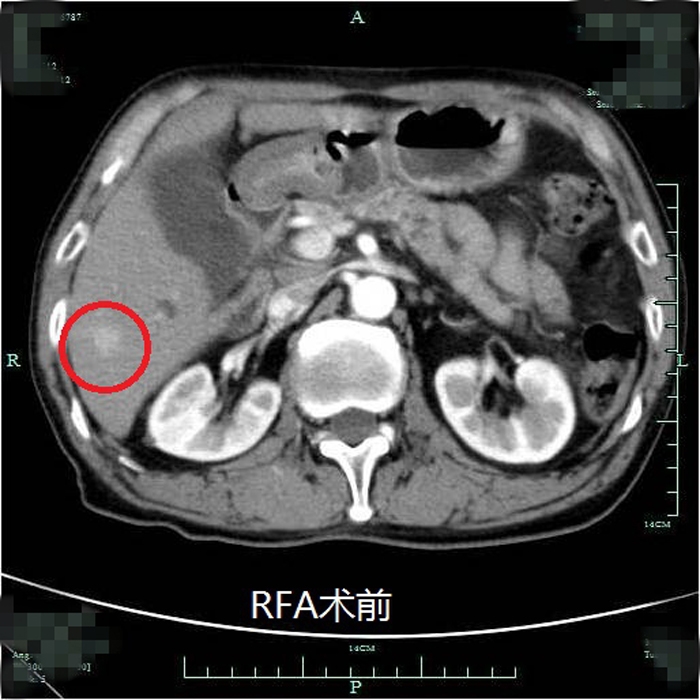

患者術(shù)前尾狀葉腫塊CT顯影

典型射頻治療患者術(shù)前術(shù)后效果對(duì)比(非該尾狀葉患者)